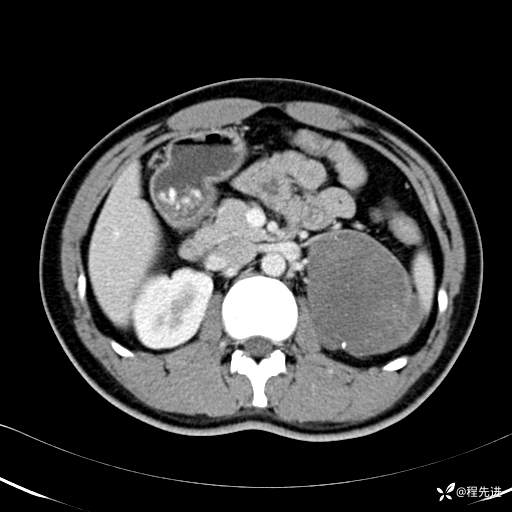

CT平扫:(CT值:平扫,27HU,动脉期,27HU,门静脉期,31HU,平衡期,32HU)

CT增强:

动脉期: